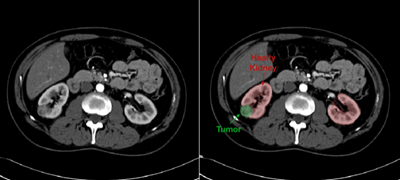

Accurate Diagnosis of Kidney Cancer

Kidney cancer does not always show symptoms, so accurate testing is essential for a diagnosis. Hackensack Meridian Health uses the most advanced imaging along with other tests to diagnose kidney cancer.

With the most advanced MRI and CT technology, Hackensack Meridian Health uroradiologists (radiologists who specialize in conditions of the urinary tract) partner with your care team to make an accurate diagnosis. This includes:

- Determining whether a mass is solid (which can indicate a cancerous or non-cancerous tumor) or fluid filled (which can indicate a non-cancerous cyst)

- Diagnosing with great precision the size and stage of any tumors in the kidney

- Distinguishing tumors that need surgery and tumors that are candidates for active surveillance

- Detecting any cancer that has spread beyond the kidney